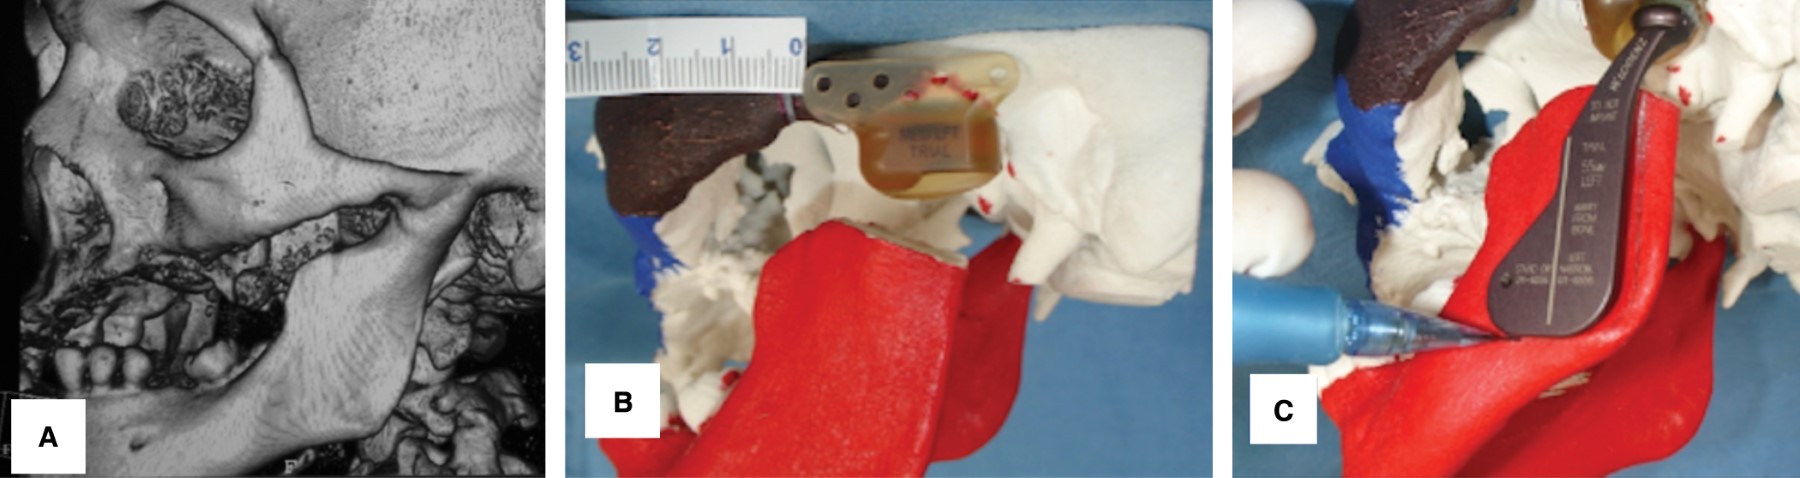

Se trató de una mujer de 41 años, la cual en 1999 inició su padecimiento de anquilosis temporomandibular izquierda secundario a herida por proyectil de arma de fuego con orificio de entrada a nivel de ATM izquierda. Posteriormente presentó dolor intenso de tipo punzante en la zona preauricular izquierda, imposibilidad de adecuada alimentación y una apertura limitada de 10 mm. En la tomografía se observa una anquilosis tipo IV según Sawhney de ATM izquierda, en donde se observa una fusión ósea ancha, que se extiende desde la rama y cavidad glenoidea, reemplazando por completo la arquitectura de la articulación (Figura 5A). Se realizó el mismo protocolo de estudio (Figura 5 B y C). Con mismo manejo quirúrgico mediante anestesia general balanceada, se realiza abordaje preauricular y submandibular descritos en el caso 1, posteriormente se realiza artroplastia de ATM, coronoidectomía, ajuste y colocación de acetábulo y prótesis condílea de stock (Biomet Microfixation), coincidiendo con la planeación previa en la estereolitografía (Figura 6 A-C).

Figura 5

Figura 6